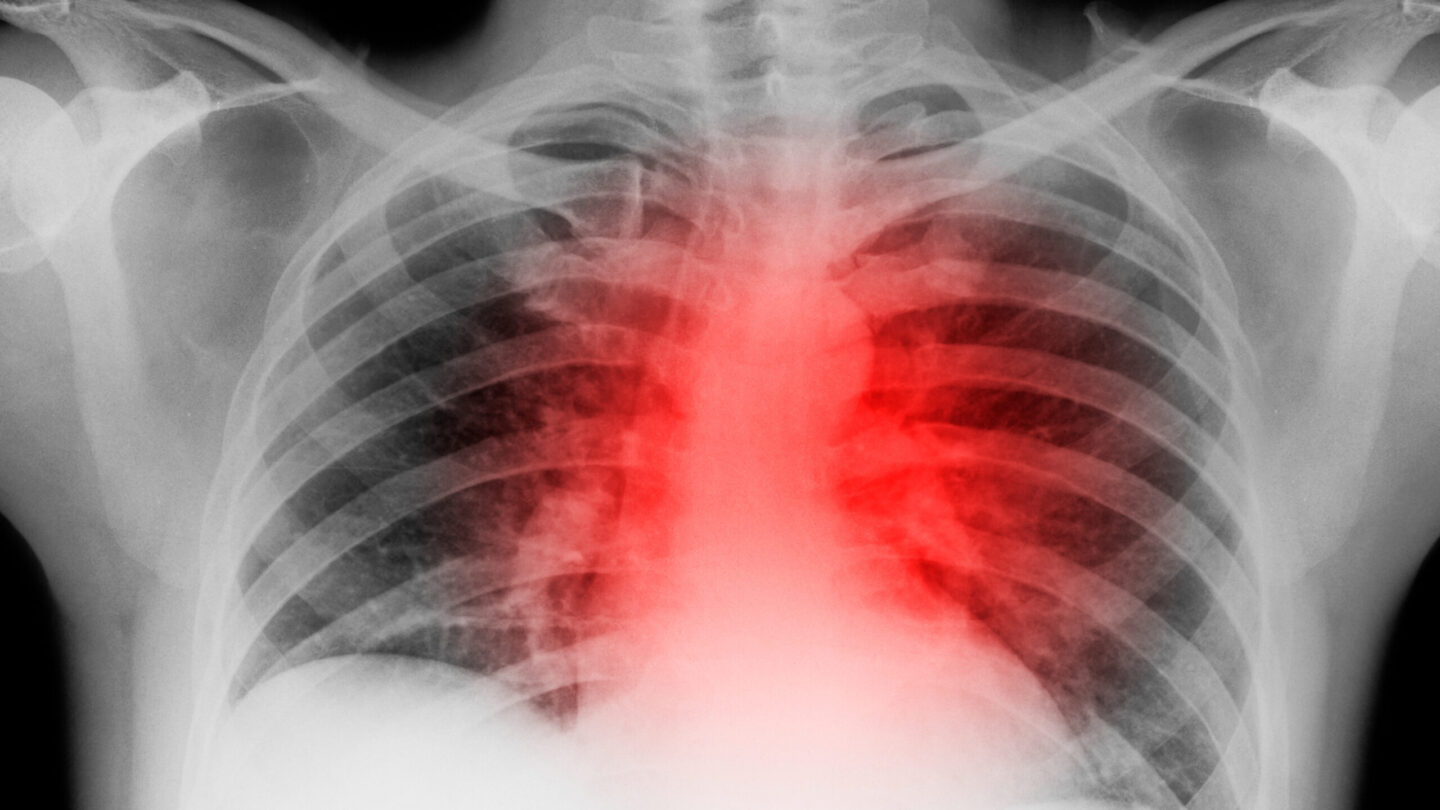

Robi Tamargo never worried much about her heart.

The 61-year-old had started running competitively in middle school, played Division 1 sports in college and kept up her exercise routine throughout her life, working out regularly at her local gym before work.

But that changed in the spring of 2020 — when she got COVID.